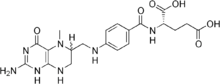

Levomefolic acid

Levomefolic acid (INN) (also known as L-5-MTHF, L-methylfolate and L-5-methyltetrahydrofolate and (6S)-5-methyltetrahydrofolate, and (6S)-5-MTHF) is the primary biologically active form of folate used at the cellular level for DNA reproduction, the cysteine cycle and the regulation of homocysteine. It is also the form found in circulation and transported across membranes into tissues and across the blood-brain barrier. In the cell, L-methylfolate is used in the methylation of homocysteine to form methionine and tetrahydrofolate (THF). THF is the immediate acceptor of one carbon units for the synthesis of thymidine-DNA, purines (RNA and DNA) and methionine. The un-methylated form, folic acid (vitamin B9), is a synthetic form of folate, and must undergo enzymatic reduction by methylenetetrahydrofolate reductase (MTHFR) to become biologically active.[1]